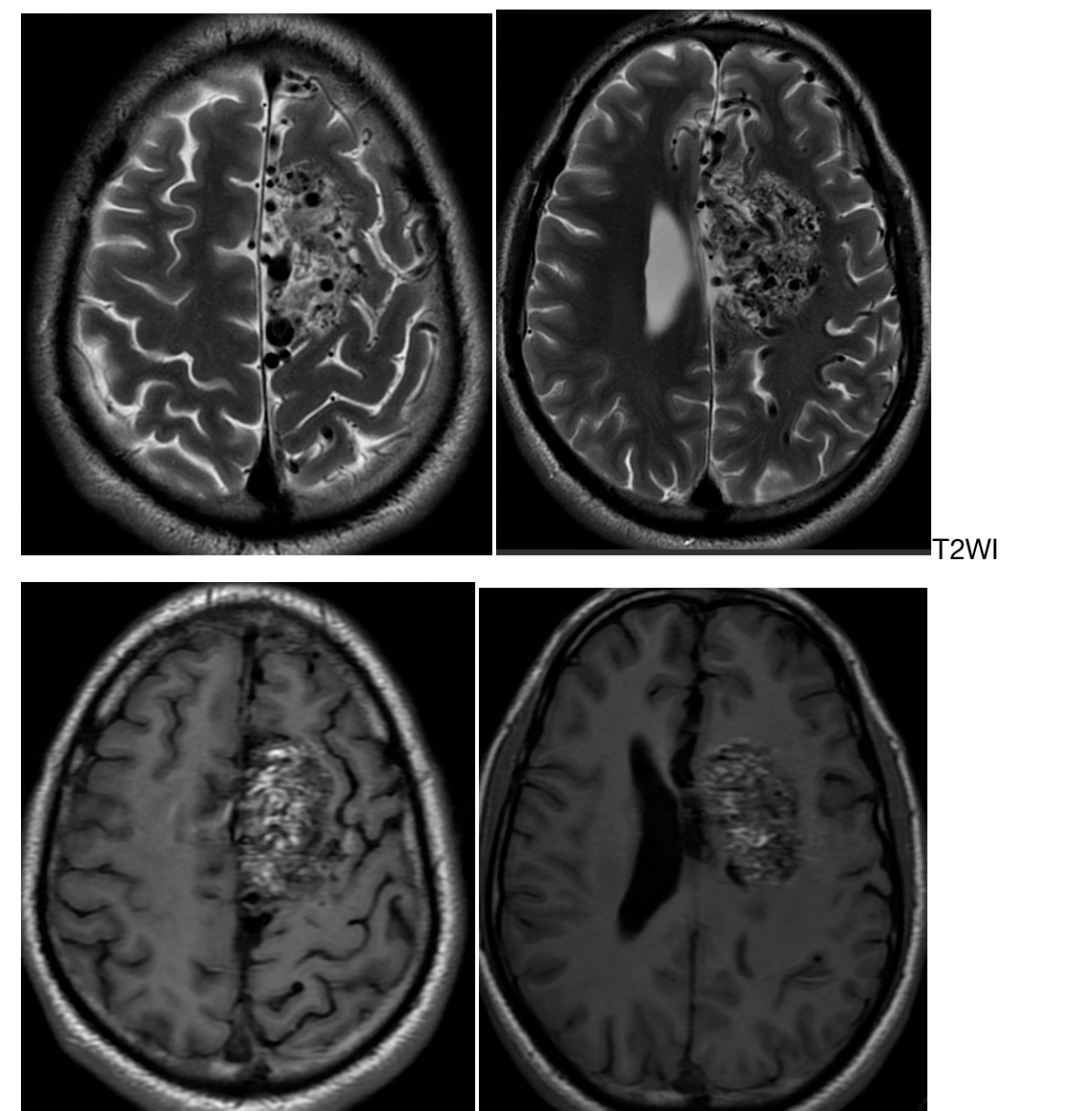

胼胝体动静脉畸形

小儿脑动静脉畸形急诊手术治愈病例

介入栓塞治疗4岁儿童胼胝体头端动静脉畸形1例